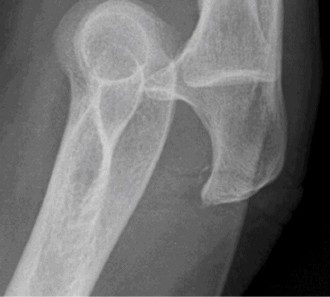

Understand the outcome and prognosis of adhesive capsulitis? CASE 30 Dr. Robert J. Stewart A 44-year-old, right-hand-dominant male with well-controlled diabetes and hypertension presents to clinic with left shoulder pain. The patient denies a history of trauma or injury. He localizes his pain over the superolateral aspect of the shoulder, and it radiates to the deltoid insertion. He has experienced pain over the past few months, but it has progressively become more severe over the past several days. He has difficulty sleeping and with range of motion because of severe pain. While examining the patient, he has a warm and tender left shoulder, and while performing a range of motion evaluation, the patient notes that he has a sensation of “catching.” He has a positive Hawkins sign, negative drop arm test, and pain with a cross body adduction test. A radiograph of the left shoulder is shown in Figure 2–77.

Figure 2–77

What is the most likely diagnosis?

- Rotator cuff arthropathy

- Septic arthritis

- Acromioclavicular (AC) joint osteoarthritis

- Calcifying tendinitis

- Glenohumeral (GH) joint osteoarthritis

Discussion

The correct answer is (D). Calcific tendonitis (CT) is a condition characterized by the buildup of calcium hydroxyapatite crystals within tendons. It typically occurs around synovial joints and has been reported in the hip, paraspinal muscles, hand, and foot. It most frequently occurs around the shoulder in patients who are 30 to 50 years old. No one over the age of 71 has been recorded having this condition. Degenerative calcification and reactive calcification have both been proposed as mechanisms for the deposition of calcium. Although the etiology is not understood, most believe that it is a reactive mechanism involving an active, cell-mediated process in a viable tendon. The cell-mediated process has been divided into three distinct phases: precalcific, calcific, and postcalcific. Depending on the stage, imaging, and physical examination characteristics can differ. The calcific stage can be further classified into three phases: formative, resting, and resorption. Rotator cuff arthropathy is seen in older patients with chronic, massive, rotator cuff tears and glenohumeral osteoarthritis. Septic arthritis can look similar to CT, but this patient has had a history of shoulder pain without fever or other risk factors for infection. Answers C and E are incorrect because there are no signs of osteoarthritis of the AC or GH joint on radiograph or physical examination.

Which structure is most likely to be affected on the basis of the information obtained thus far, including the radiograph Figure 2–77?

- Deltoid

- Infraspinatus

- Supraspinatus

- Teres minor

- Subscapularis

The correct answer is (C). Calcific tendonitis (CT) is most often localized in the supraspinatus tendon. Radiographic views should include a true AP in internal and external rotation, axillary, and scapular-Y to evaluate for calcium deposits in the tendons of the rotator cuff. There are no reports of the deltoid muscle being involved in CT. Radiographs also help to distinguish resorptive and formative phases. Two radiographic types have been described: Type I (associated with the resorptive phase and acute pain) is a deposit that is fluffy or fleecy in appearance with a poorly defined periphery. Type II (associated with the formative phase and chronic pain) has discrete, homogeneous deposits that have a well-defined periphery.